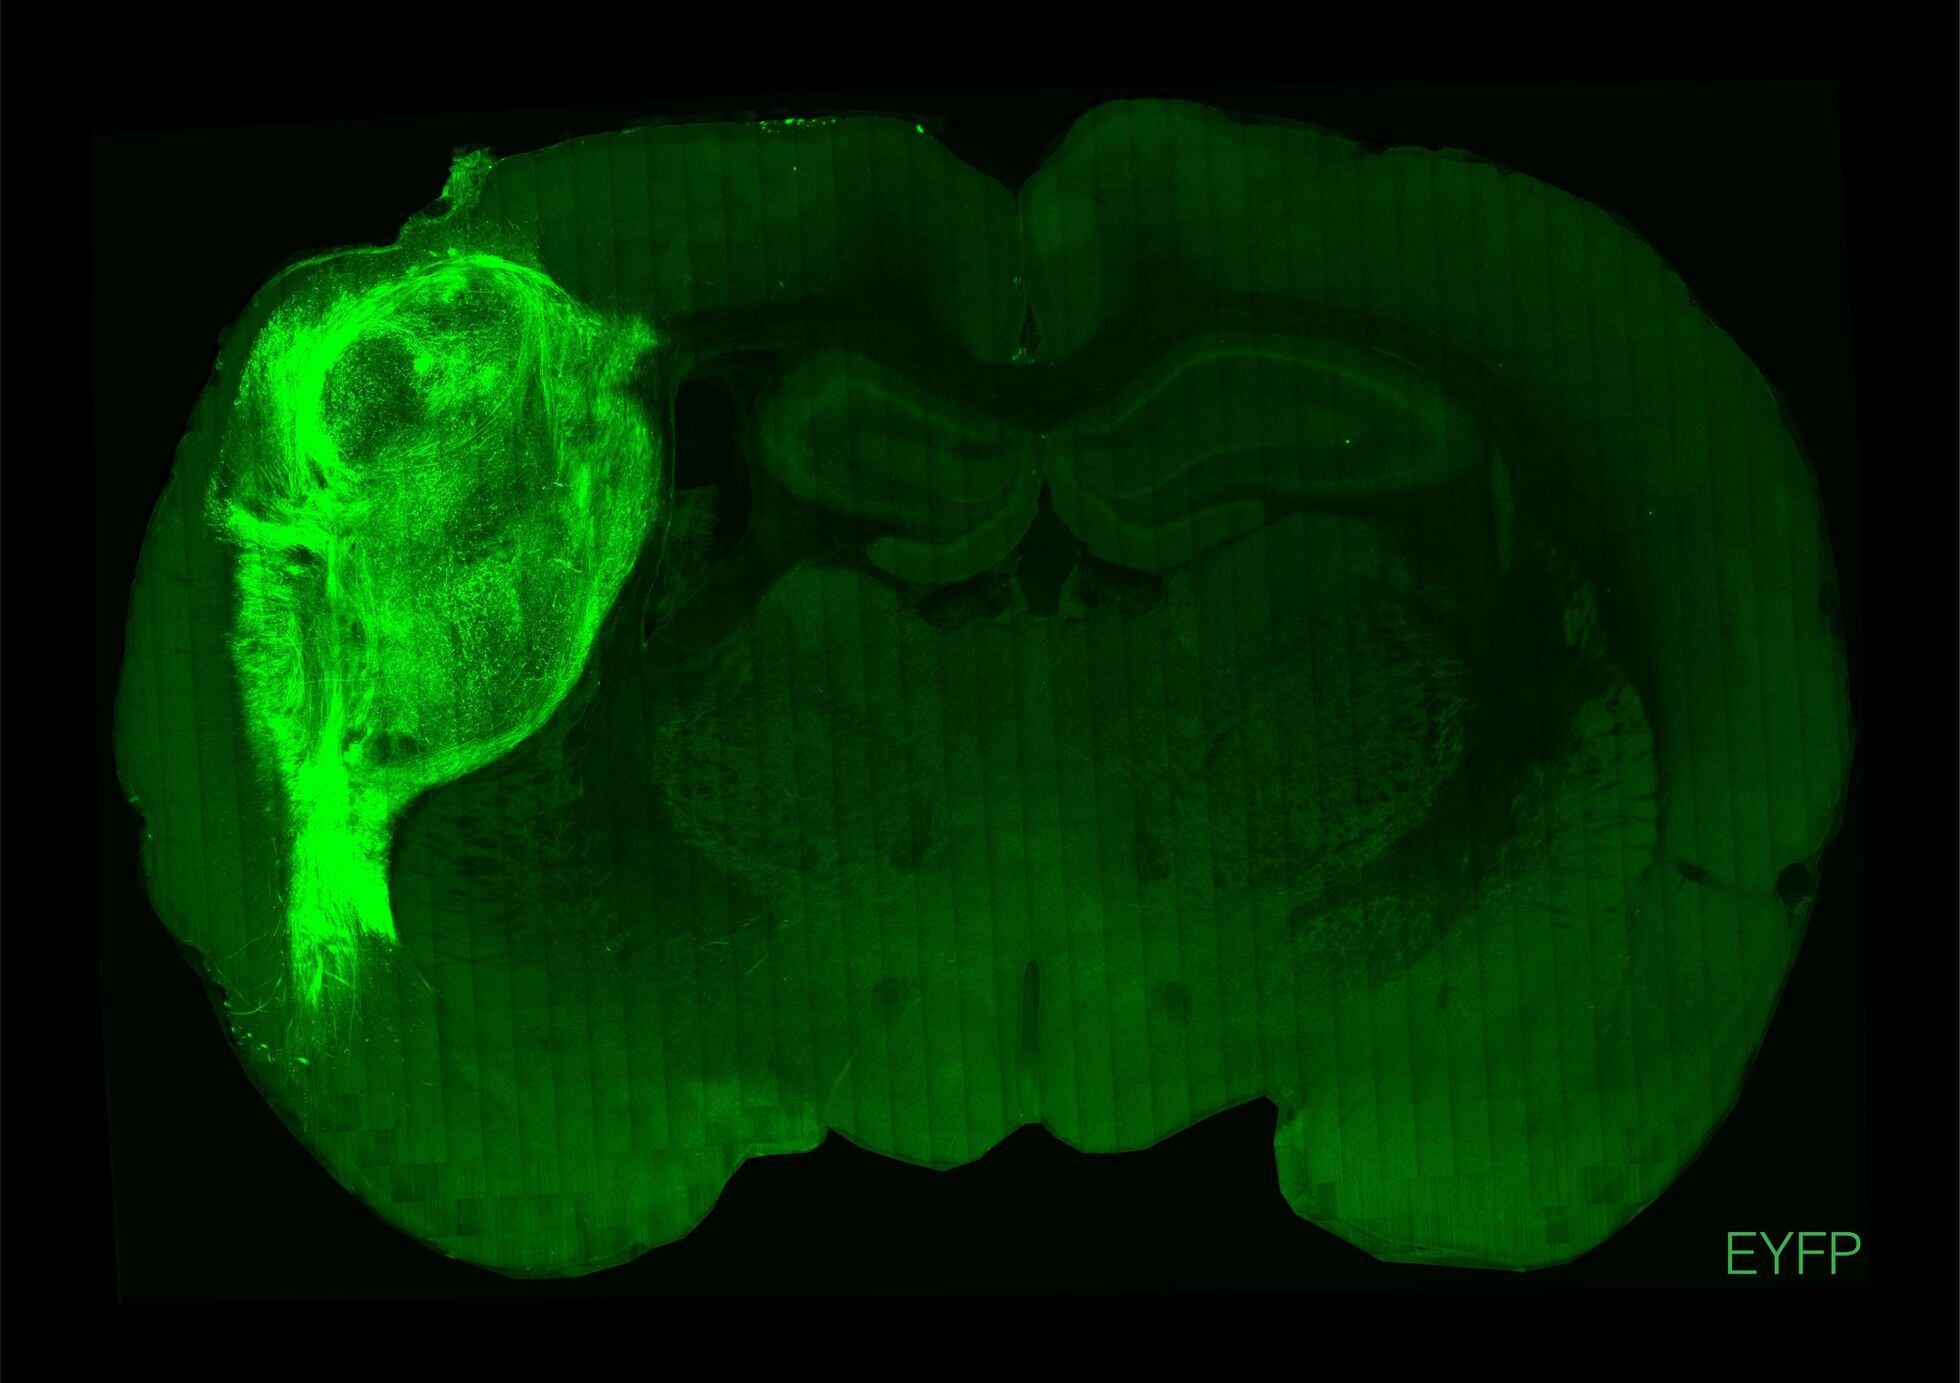

Para superar estas limitaciones, los investigadores implantaron agrupaciones de células cerebrales humanas, llamadas organoides, en los cerebros de ratas recién nacidas, informó la agencia de noticias AFP.

“Al transpantarlos en esta etapa temprana, vimos que estos organoides llegan a tamaños relativamente grandes, se vascularizan de la rata y pueden cubrir un tercio del hemisferio cerebral” del animal, añadió Pasca.